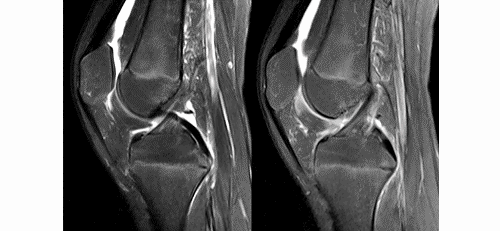

4.gif

ACL最好的观察层面:最好的观察层面是斜矢状面,同时需要结合横断面和冠状面。